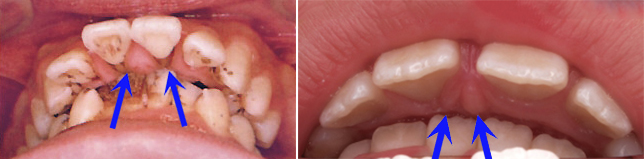

齒列不整,特別是存有牙齒擁擠的齒列不整,極易造成食物堆積的死角而引發蛀牙(圖2)。

(圖2)齒列不整,特別是存有牙齒擁擠的齒列不整,極易造成食物堆積的死角而引發蛀牙。藍色圈標定蛀牙位置。